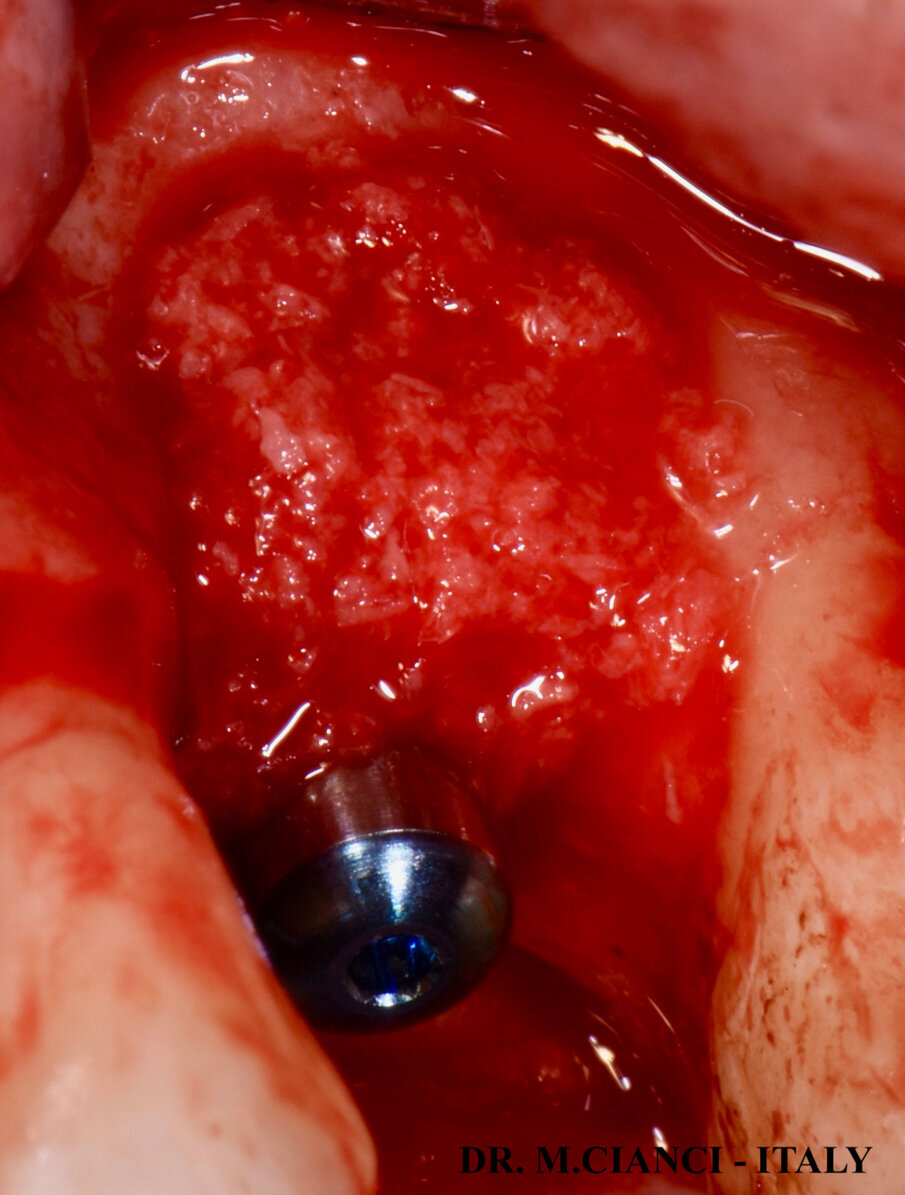

Sollevato un lembo a spessore totale vestibolo-palatale sono state utilizzate frese di diametro progressivo sottopreparando il tragitto implantare al fine di ottenere una stabilità primaria necessaria ad eseguire il carico immediato: ultima fresa di diametro 4,8 mm utilizzata solo fino a 4 mm di profondità sottopreparando l’apice del tunnel osseo prima di inserire l’impianto. Gli ultimi 0,5 mm sono stati fresati con una speciale fresa a taglio frontale di diametro 4,5 mm che ci ha permesso di sollevare la membrana di Schneider mantenendola integra (Fig. 6). A questo punto, una volta verificata la negatività della manovra di Valsalva, è stata inserita sul fondo della preparazione una membrana di fibrina autologa elaborata con la frazione 1 del PRGF Endoret® , meno ricca di fattori di crescita piastrinici, a protezione della membrana sinusale e con un condensatore abbiamo eseguito una lieve pressione al fine di scollare la membrana a questo livello: il Sinus Lift è stato completato inserendo una piccola quantità di biomateriale autologo mischiato con la frazione 2 di PRGF più ricca di fattori di crescita13. L’impianto corto 5.5 x 7,5 mm è stato avvitato infine con un torque di 40 NCM e lasciato volontariamente esposto extra-cresta per 1 mm in sede vestibolare e 2 mm in quella palatale (Fig. 7). Abbiamo poi completato la rigenerazione vestibolo-palatale utilizzando sempre l’osso autologo del paziente mischiato alla frazione 2 di PRGF e coperto gli innesti con uno primo strato più profondo di coagulo frazione 2 ed un secondo strato più esterno di membrana di fibrina frazione 1 (Figg. 8, 9).

Fig. 8 - GBR con osso autologo e PRGF® frazione 2.

Fig. 9 - Membrane di PRGF® frazione 2 e 1.